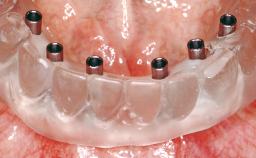

Conventional Loading of Eight Implants in the Maxilla and Final Restoration with a Full-Arch Gold-Ceramic FDP

# of Implants | 8 |

Attachment | One-Piece |

Abutment Type | Standard |